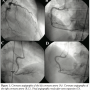

Coronary angiography revealed a normal left coronary artery (Figure 1A). The right coronary artery (RCA) was catheterized using a JR4 6 Fr guiding catheter. However, during attempts to engage the catheter into the ostium of the RCA, significant pressure damping was observed, subsiding with catheter withdrawal. Following a trial contrast injection in the RCA, haziness was temporarily observed in the right posterior lateral branch. Subsequently, the patient was spontaneously restored to sinus rhythm with simultaneous resolution of the ST-segment elevation. Angiography of the RCA did not reveal any obstructive lesions or haziness (Figures 1B and 1C), despite the fact that pressure damping was still present during engagement of the ostium. This raised suspicion of thrombus at the ostium of the vessel. Contrast injection was performed with the catheter resting outside the ostium of the RCA, and a focal contrast deficit was then observed (Figure 2A).

A decision was made to proceed with manual aspiration of the thrombus. A guidewire was inserted into the RCA and manual aspiration with a 10 mm syringe was performed using the guiding catheter, resulting in extraction of small amounts of thrombus. Optical coherence tomography (OCT) was then performed in the proximal 25 mm of the RCA using the C7 LightLab system (LightLab Imaging) and the corresponding intravascular OCT catheter (C7 DragonflyTM). OCT examination revealed the existence of small fragments of thrombus near the ostium of the vessel and the absence of any atheromatic changes of the vascular wall, or any evidence of spontaneous dissection (Figures 2B and 2C). Then, we proceeded with stenting of the RCA ostium using a 4 mm/16 mm Promus stent (Boston Scientific), with a good angiographic result (Figure 1D).